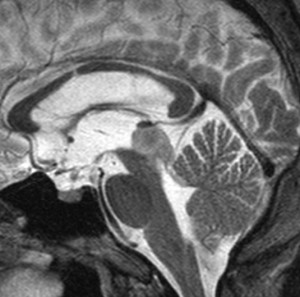

15歳で水頭症で発症して進行した例

手術摘出した方が良い例です。

毛様細胞性星細胞腫であり,基本的には初回手術で全摘出できるのですが,現実的には,技術的に難しすぎるので部分摘出で終えることが多いでしょう。この子は,15歳の時に閉塞性水頭症のために,頭痛,嘔吐,意識障害,瞳孔不同となりました。開頭部分摘出術と第3脳室開窓術で回復して,その後にカルボプラチンとビンクリスチンの化学療法を受けました。

でも腫瘍増大が止められずに,発症1年後に54グレイ30分割の放射線治療を受けています。さらにその半年後くらいから再増大しましたが,スードプログレッションと考えられました。上左MRIは放射線治療前,上右MRIは放射線治療1年後です。毛様細胞性星細胞腫は放射線治療後に一過性増大(多くはのう胞性増大)することが多いです。

のう胞性拡大が止まらず,発症3年後にまた再開頭手術 (left occipital transtentorial approach) で亜全摘出しました。右は術後の画像です。初発時の最初の手術で亜全摘出あるいは全摘出 gross total removalできていればと思える例です。